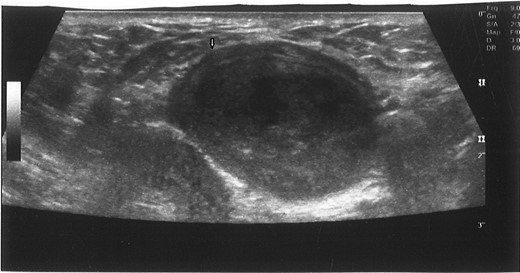

Patient was started on broad-spectrum antibiotic (Ertapenem & Vancomycine). Percutaneous ultrasound-guided aspiration drainage was done and pus was drained (Fig. 2) and sent for microscopy, culture and sensitivity.

Ultrasound-guided puncture of the mixed echogenic cystic mass of left corpus cavernosum. White arrow: needle entry site.